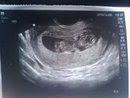

I am laying on the table pretty much exposed i shall say. This doctor appt. i get to hear the heart beat and that is all im focusing on i cannot wait to hear that sweet noise! The doctor wanted to do a transvaginal ultrasound, you know that one off the move " knocked up" ? Yeah, nuff said. Im looking up at the screen and as soon as i see this little blob i begin to have tears in my eyes. Even though its a little tiny blob its the cutest little blob i have ever laid eyes on. It wasnt moving at first but as she was moving the little stick around it did and its little legs were everywhere and its little tiny arms! It was so amazing, althought the baby is only 2.5 inches long it was the best thing i have ever seen! I looked up at thayn and caitlin and both were smiling and it was just perfect! I was happy! After the Doc gets some good measurments of the baby and prints some pics i am able to get up and dressed. She tells me that i am completely healthy and that everything with me is great! I was so happy to hear that because of course i want to be healthy for the baby. She told me that i should have my appts at schofield since i looked great and from what baby looked like so did he/she. so i made my 20 week ultrasound appt for the 2nd of Nov. So i will keep you posted on my adventures of pregnancy, for those who read!